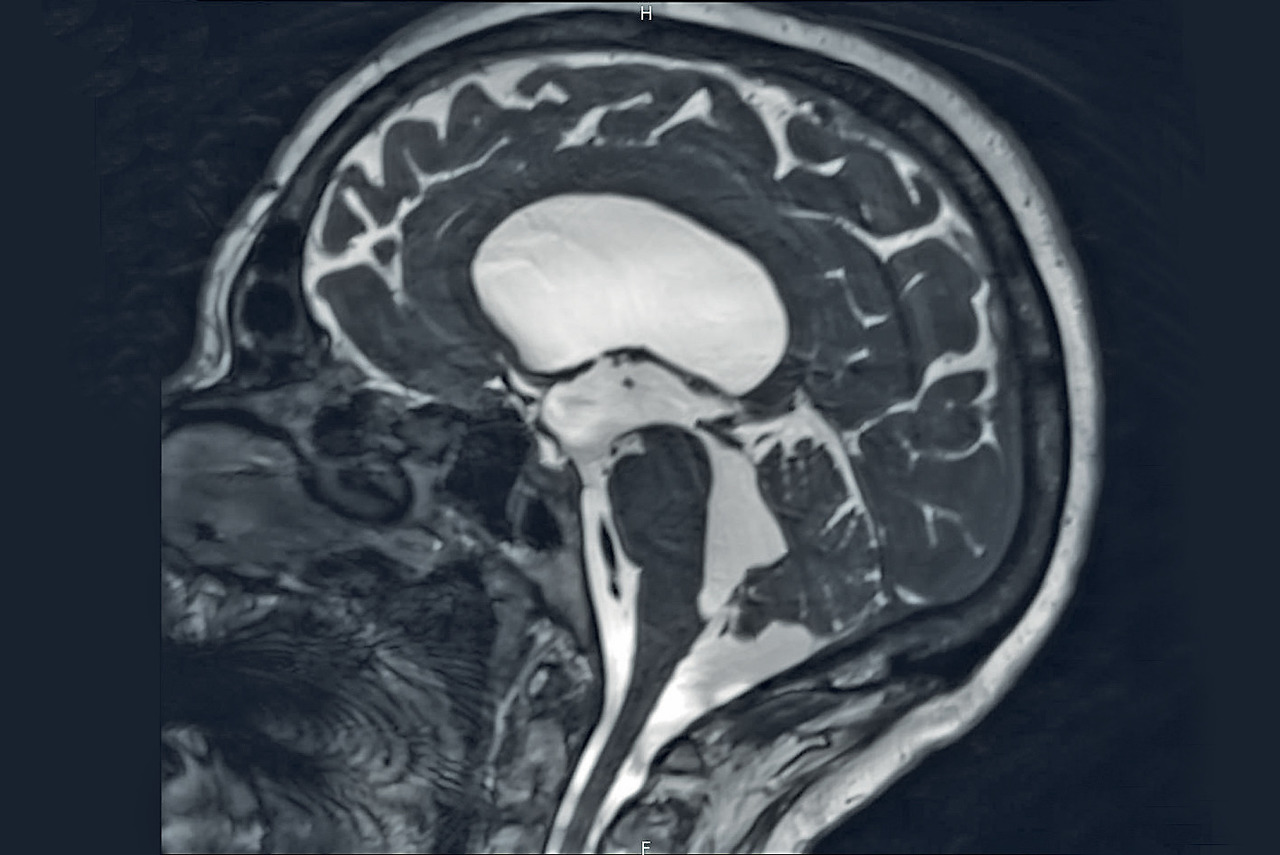

Témoignant d’une altération de cette hydrodynamique, l’hydrocéphalie augmente le volume ventriculaire,2 ce qui élève la pression dans cet espace fermé et inextensible, avec un risque important d’hypertension intracrânienne (HTIC) et de troubles neurologiques (ischémiques et par compression vasculaire).

Obstacle à la circulation du LCR, majoritairement (encadré). Selon la position de l’obstacle à l’écoulement et le nombre de ventricules dilatés, l’hydrocéphalie est dite bi-, tri- ou tétra-ventriculaire (fig. 1). La cause peut être malformative (sténose de l’aqueduc de Sylvius par exemple), vasculaire (hémorragie sous-arachnoïdienne, intraventriculaire), infectieuse (méningite, méningo-encéphalite), tumorale, dégénérative ou post-traumatique (sévère).

L’IRM cérébrale est nécessaire en cas d’hydrocéphalie triventriculaire (les 2 ventricules latéraux et le 3e). Elle met en évidence un obstacle à l’écoulement du LCR (+++), son flux étant analysé grâce à des séquences dynamiques. Après chirurgie, on y contrôle l’efficacité d’une procédure de ventriculocisternostomie. Elle complète le bilan en cas de tumeur cérébrale et confirme une imperforation des trous de Magendie et/ou de Luschka (orifices de sortie du 4e ventricule ; fig. 2), essentiellement congénitale (malformation de Dandy-Walker, agénésie ; encadré).